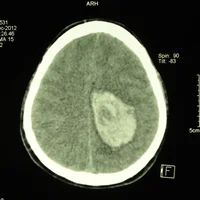

Hémorragie intracérébrale

Hématomes intracrâniens